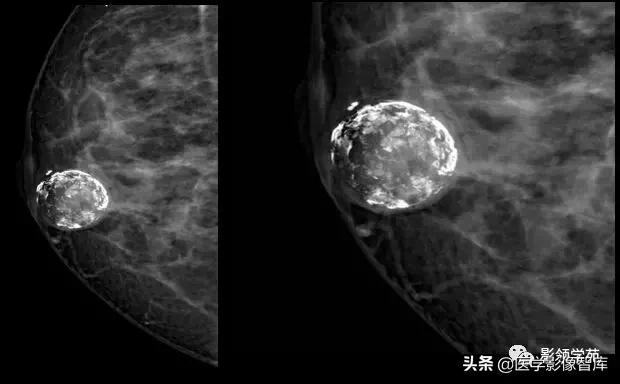

4. Coarse or 'Popcorn-like'

纤维腺瘤(fibroadenoma):典型的粗大爆米花样钙化。有时在肿瘤包膜边缘形成钙化,表现为环状钙化。与恶性钙化相比,纤维腺瘤的钙化通常较粗大于 2 mm, 分布更趋向边缘。

成簇分布,左乳退化型纤维腺瘤:

钙化略小且较密集,注意与恶性钙化鉴别。